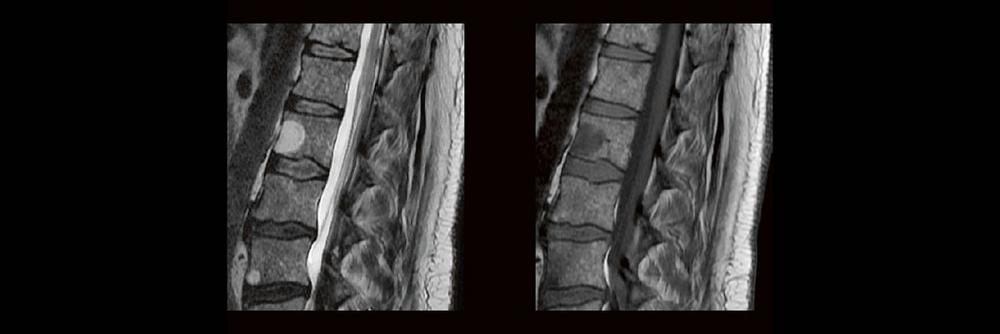

Dorina Petersen In der täglichen Routine hat man wenig Zeit, sich lange mit den Bildern zu beschäftigen, die man anfertigt. Dennoch soll man auf bestimmte Erkrankungen richtig reagieren und die Protokolle anpassen. MTR´s sind keine Ärzte, dennoch gibt es ein Krankheiten, die eindeutige Bildmerkmale zeigen. In diesem Webinar werden eine Reihe solche Erkrankungen gezeigt. Woran

Professor Dr. med. Marc Brockmann WEITERENTWICKLUNGEN VON KOPF BIS FUSS BEIM VC Oberstarzt Dr. med. Stephan Waldeck DEEP-LEARNING-REKONSTRUKTION IN DER NEURORADIOLOGIE Die CT ist ein essentielles Routine-Verfahren in der Neuroradiologie. Bei steigender Bildqualität konnte die Röntgendosis mit neuen Technologien in der letzten Dekade deutlich gesenkt werden, was für die zielgerichtete und möglichst schonende Behandlung von